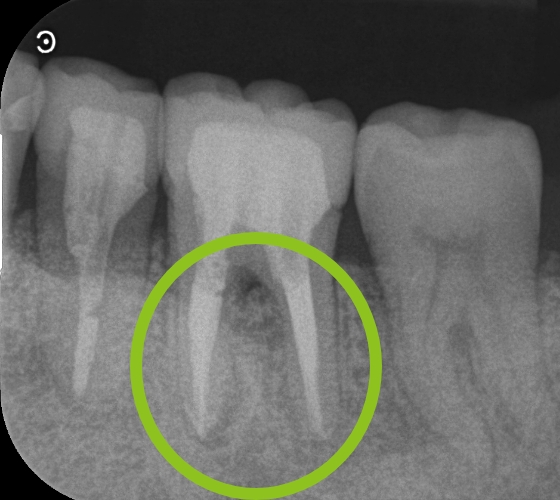

55歳男性 腫れて痛む

治療前

ラバーダム防湿下で根管治療中

治療後

治療内容 以前他院で根管治療(根の治療)をした歯が、歯肉の腫れと排膿(膿が出る)や痛みが再発した症例です。

レントゲン写真で根尖部(根の先)に明らかな透過像(病変)を認めたため、再根管治療(根の治療)を行いました。

マイクロスコープ(顕微鏡)を用いて、ラバーダム防湿下で根管内を徹底洗浄・消毒後、根管を緊密に再封鎖しました。

治療後は腫れや痛みが速やかに消失し、レントゲン上でも根尖部(根の先)の透過像(病変)が著しく縮小したのを確認しました。

治療回数 2~5回

治療費用(総額)

保険治療でおおよそ2,000〜5,000

(根管治療のみ。被せ物は別途かかります。治療時の金額であり、時期や手法により異なる場合があります。)

副作用・リスク ・感染の再発により、再治療または外科的手術が必要となる可能性があります。